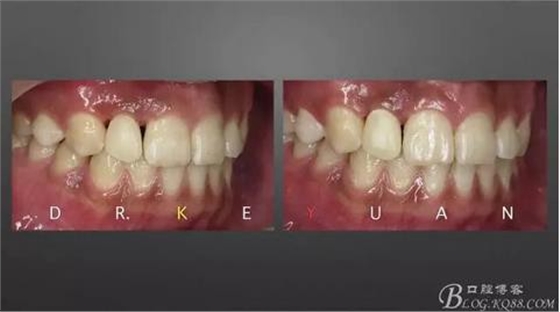

CASE 4—18歲少年,冠折后半年來診

1、術(shù)前比色